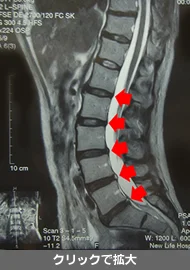

MRIを撮影しましょう

首の椎間板、胸の椎間板、腰の椎間板に異常があると、首の一部分のみの動きが大きくなり、むち打ち症を悪化させます。

首の椎間板変性

首の骨に椎間板の薄い部分があると、その部分のぐらつきが多くなり、むち打ち症が長引きます。

腰の椎間板変性

腰の骨に椎間板損傷があると、首を振られることで髄膜が引っ張られるので、ヘルニアの悪化や脳脊髄圧減少症の原因になることもあります。

椎間板変性があっても、健康な背骨の部分の動きを取り戻し、変性部分の運動を代行できるようになれば、十分な回復が望めます。MRIで異常のない場合は、まずは不安と心配を解決しましょう。